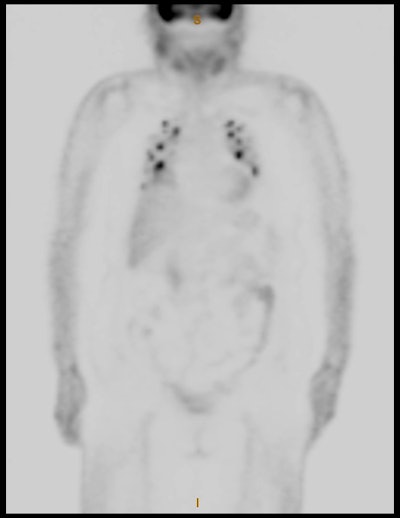

I-123 Diagnostic scan: The diagnostic scan on the left was performed using I-123. Extensive pathologic nodal uptake is seen within the lower neck and mediastinum. A separate focus of increased tracer accumulation is seen over the right upper abdomen (not seen on post-therapy scans- possibly due to superimposed liver activity). The post-I-131 therapy scan (right) demonstrates uptake in the nodal metastases and diffuse hepatic tracer activity due to metabolism of radiothyroxine. |

|